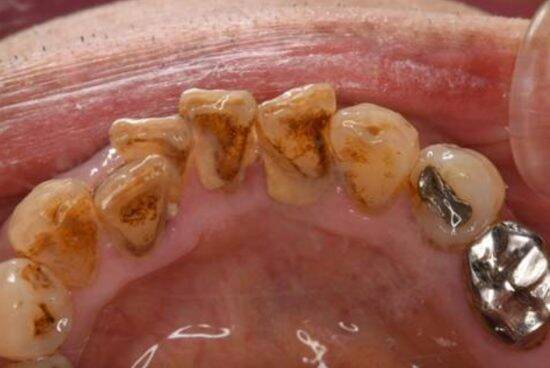

・歯石やプラークの除去による口腔内の清潔維持

一時的な改善が見られても、歯磨きが面倒になったりモチベーションの低下が考えられ、リスクがまだ高い状態であることから、しばらくは短い間隔での検診を行います。

また、高齢者は歯茎の退縮やドライマウス、義歯のトラブルなども起こりやすくなります。仕事を退職され、家で過ごす日が多くなると、歯磨きも疎かになってしまう場合も多いです。